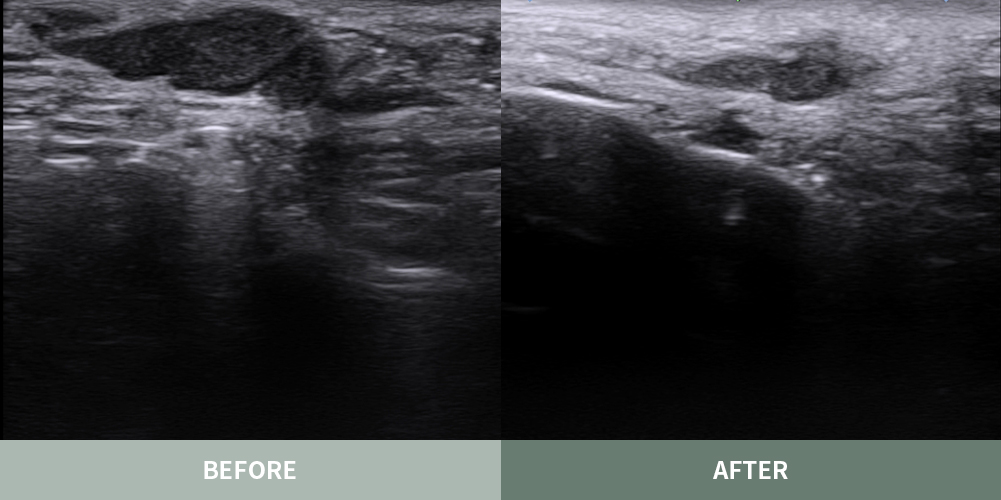

마이너스핏 프로그램은 얼굴이나 몸의 유착 조직이나 섬유화된 결절 부위를

초음파로 정밀하게 진단 후 부작용이 발생하기 전의 자연스럽고

아름다운 본래의 피부로 복원하는 흉살 치료 프로그램입니다.

대표원장 촉진 및 초음파 진단

흉살 조직에 대한 경험과 이해가 풍부한 고정아 대표원장이

부작용의 상태를 직접 파악하고 정확하게 진단합니다.